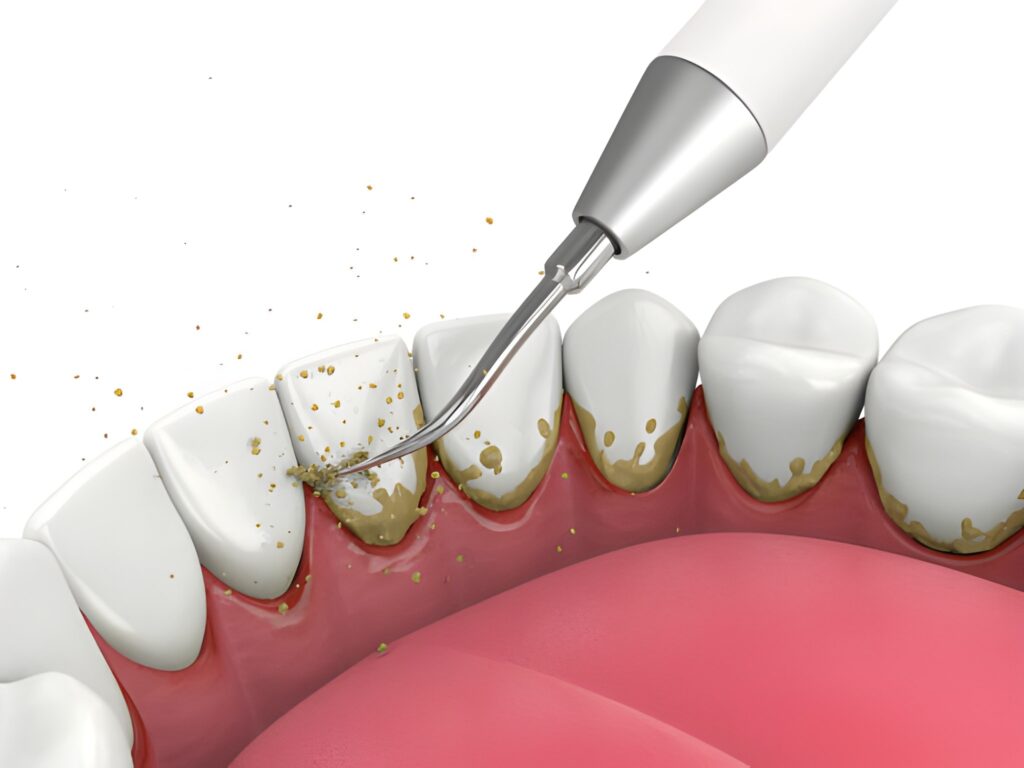

We wholeheartedly champion a great at-home routine, brushing for two minutes, twice a day, and flossing daily. That effort is essential. However, even the most meticulous brusher cannot fully remove the hardened build-up known as tartar (or calculus).

Plaque is a sticky film of bacteria that forms on your teeth constantly. If left alone for just 24 to 72 hours, this plaque hardens into tartar, typically near the gum line and in those tight, hard-to-reach spots between teeth.

Here’s the problem: Tartar is a concrete-like substance that can only be removed by specialized dental tools, namely, the scalers and ultrasonic devices used by our professional hygienists.

The presence of tartar creates a rough, porous surface where even more plaque and bacteria can cling, fueling a cycle of inflammation and damage. If that cycle isn’t broken regularly, you’re on a fast track to serious oral health issues.